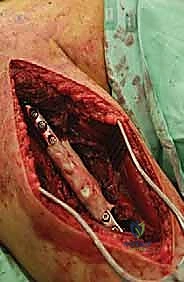

2. الاستئصال الواسع وإعادة البناء باستخدام الإسمنت العظمي والشرائح

عندما يكون الورم قد دمر جزءاً كبيراً من جسم العضد، يتم اللجوء إلى تقنية أكثر تعقيداً:

* يتم فتح شق جراحي، وعزل الأعصاب (خاصة العصب الكعبري).

* يتم تجريف الورم بالكامل (Curettage) للوصول إلى أنسجة عظمية سليمة.

* يتم استخدام مثقاب عالي السرعة لإزالة أي خلايا سرطانية متبقية، وقد تُستخدم مواد كيميائية (مثل الفينول) أو الكي الحراري لقتل الخلايا المجهرية.

* يُملأ الفراغ العظمي الكبير بـ الإسمنت العظمي الطبي (Polymethylmethacrylate - PMMA). هذا الإسمنت لا يعوض العظم المفقود فحسب، بل إن الحرارة العالية التي يولدها أثناء تصلبه تقتل أي خلايا سرطانية متبقية.

* يتم تدعيم البناء بشريحة معدنية طويلة ومسامير قوية لضمان الاستقرار الميكانيكي.